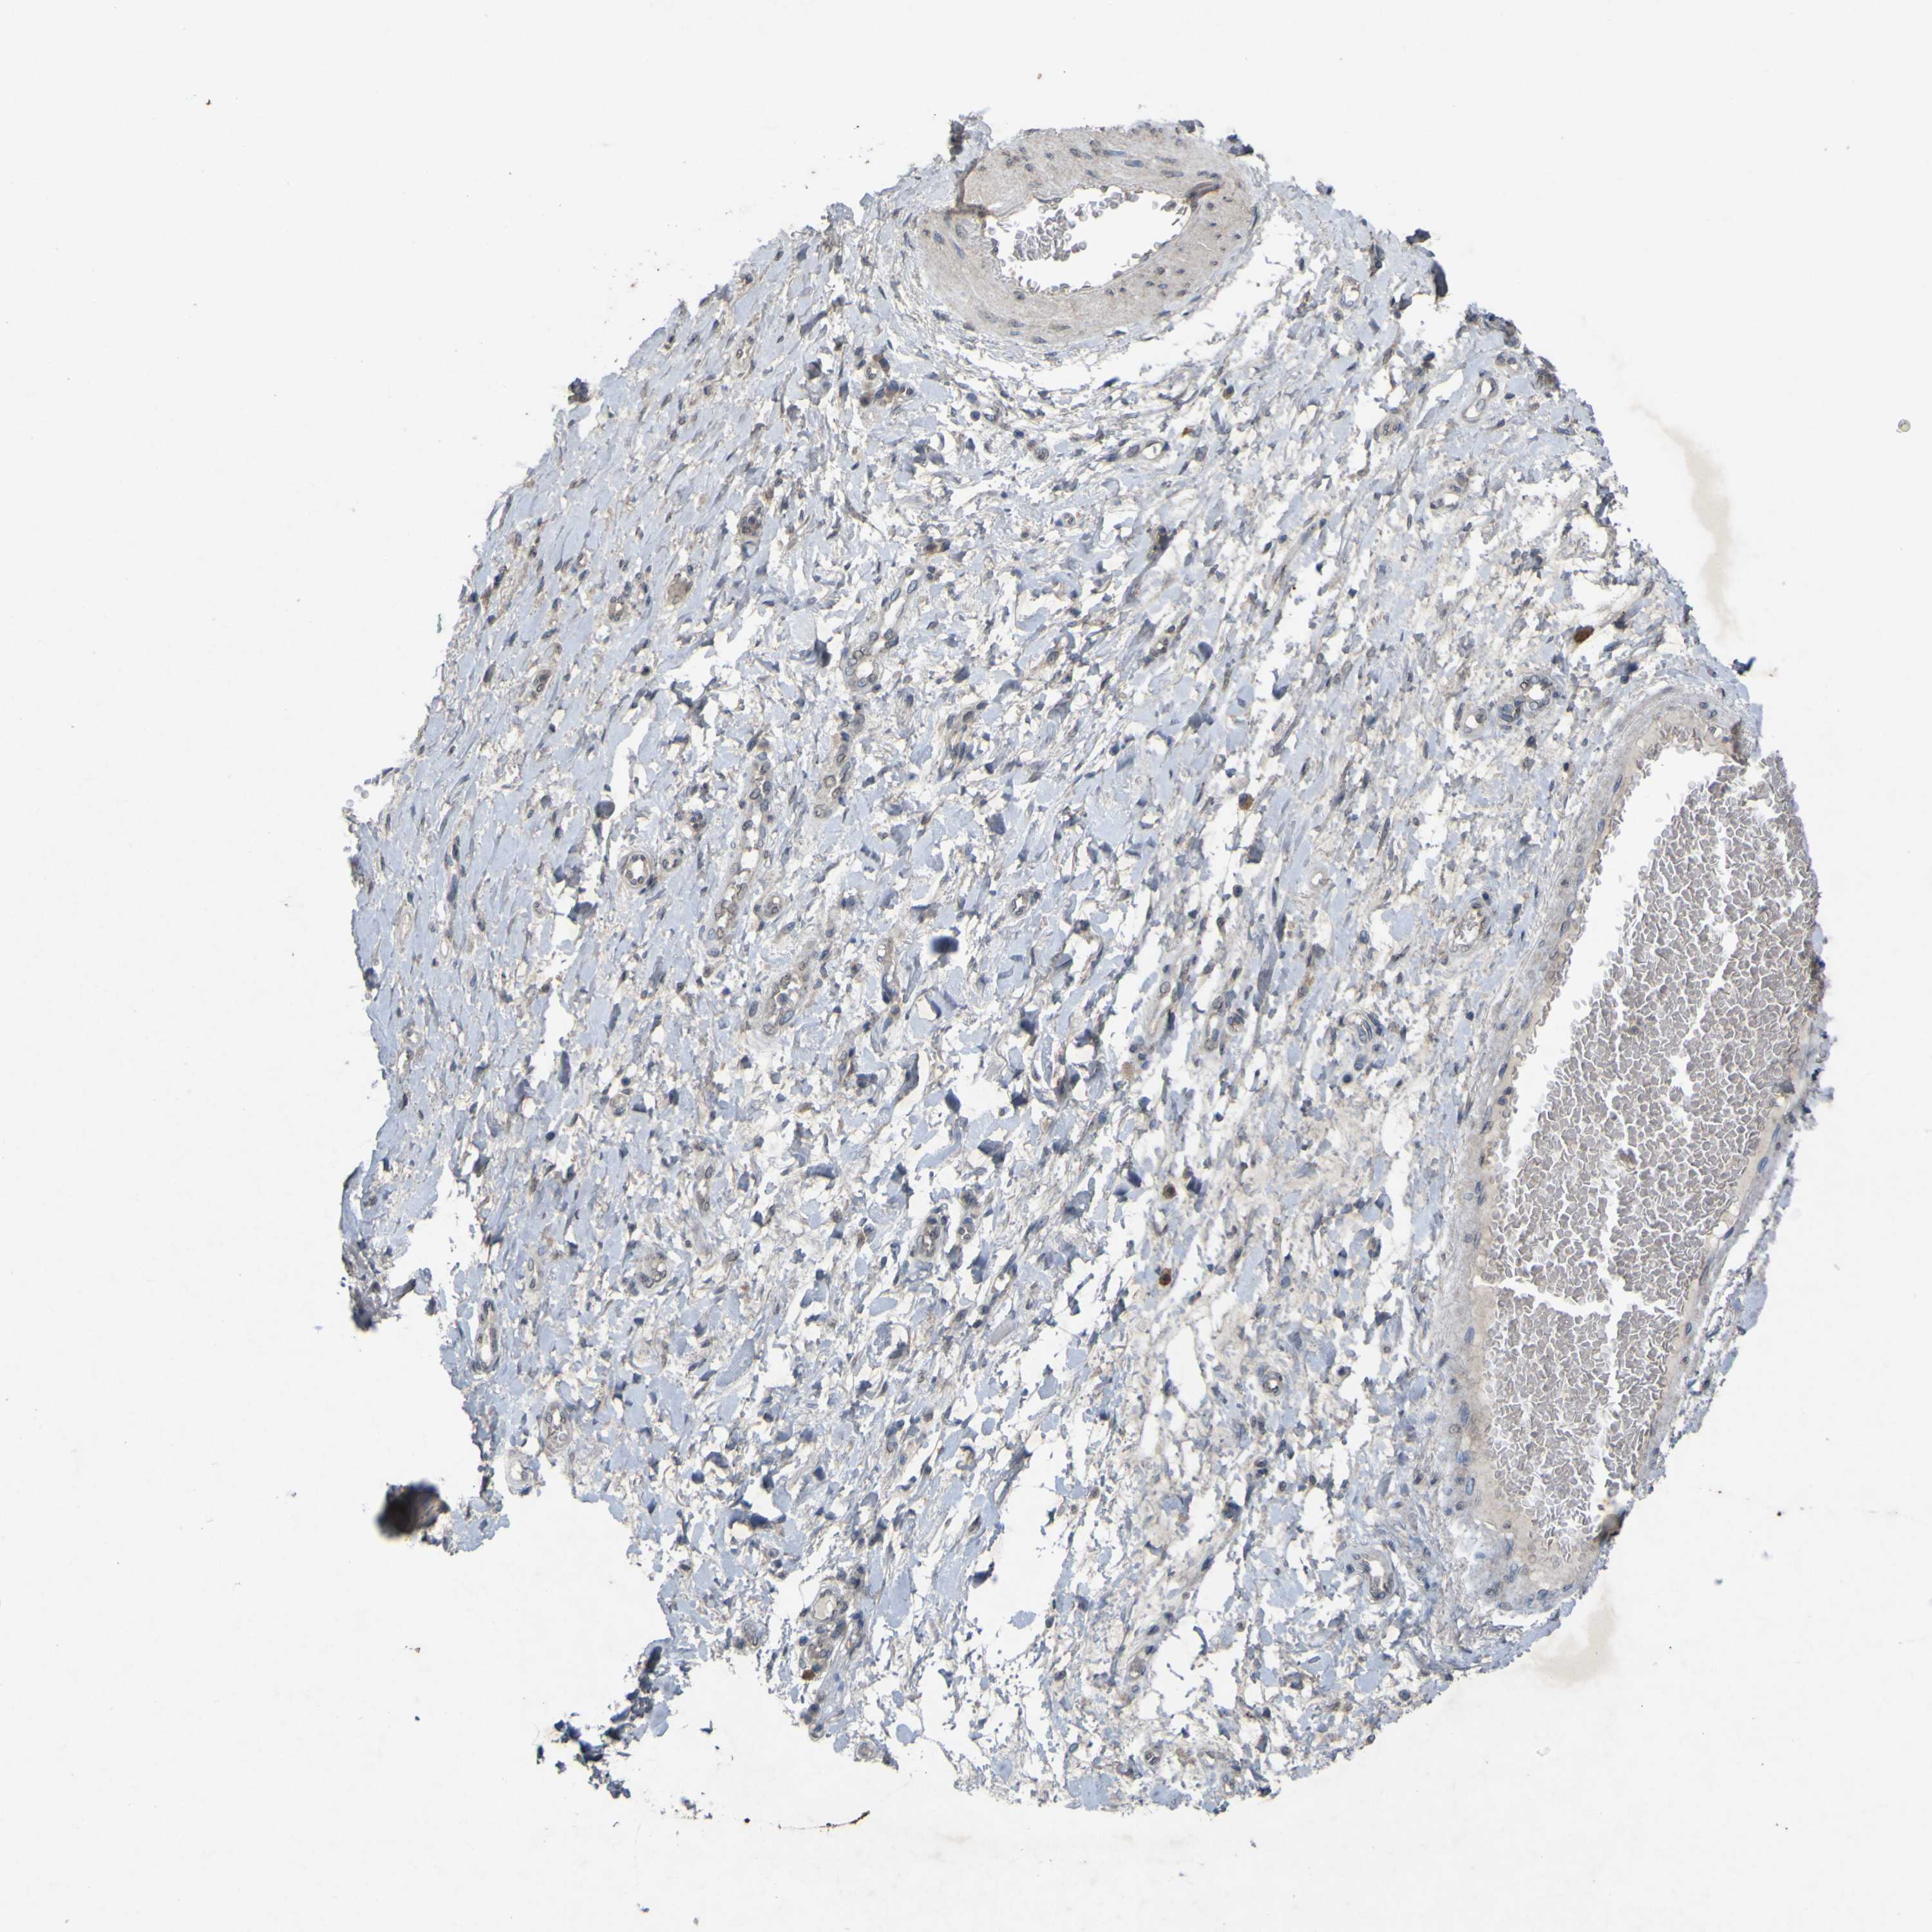

PRKCG